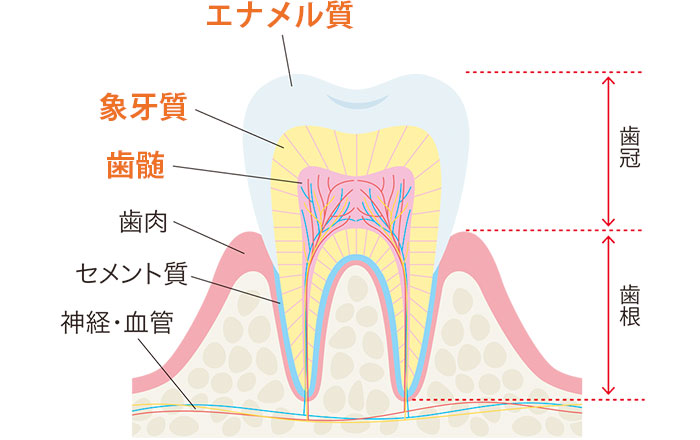

今回のテーマであるNCCLとは、虫歯以外の原因で歯の根元部分(エナメル質とセメント質の境目付近)が削れたり、欠けたりしてしまう状態のことです。

NCCLはNon-Carious Cervical Lesionsの頭文字をとった専門用語です。日本語では非う蝕性歯頚部病変(ひうしょくせいしけいぶびょうへん)と少し難しい名前で呼ばれています。う蝕とは虫歯のことなので、冒頭で触れたように、「虫歯以外の原因で、歯の歯冠の根元が欠けた状態」を指します。

歯の表面のエナメル質が削れてなくなると、その下にある柔らかい象牙質がむき出しになります。そしてフォースデンティンのコラムで解説したように、象牙質には、歯の神経へと続く小さなトンネルのような象牙細管(ぞうげさいかん)が無数に走っています。

歯の根元がえぐれると、歯の形が不自然に見えるだけではありません。むき出しになった象牙質はエナメル質よりも黄色っぽく見えます。